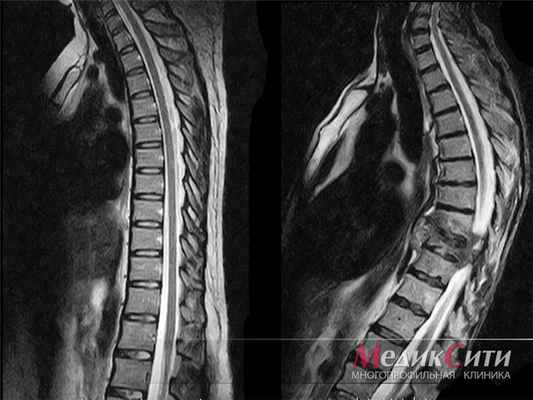

МРТ грудного отдела позвоночника: 1. норма 2. опухоль

МРТ грудного отдела позвоночника

МРТ грудного отдела позвоночника назначают пациентам с:

- демиелинизирующими процессами (рассеянный склероз, острый рассеянный энцефаломиелит). МРТ – единственный метод инструментальной диагностики и визуализации демиелинизирующих заболеваний;

- острыми нарушениями спинального кровообращения, а также сосудистых мальформаций в спинном мозге.